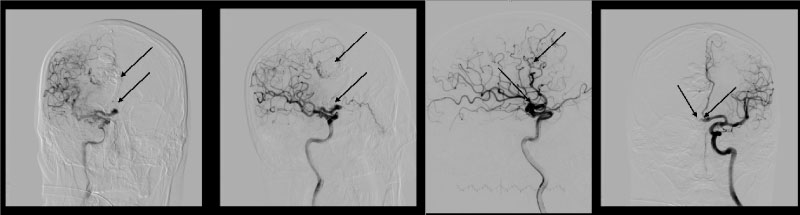

At the first stage we conducted a microcatheter Sonic® (BALT) 1.5 F into the AVM performed angiography and embolization of the AVM node with three doses of liquid embolic agent PHIL® 25% (MicroVention) (Figure 3). Then performed control angiography (Figure 4).

Figure 3: Supreselective angiography showing AVM node and embolized fistulous part of the AVM. View Figure 3

Figure 4: Control cerebral angiography showing embolized AVM and flow-related aneurysm. Left ICA. Blood flow in ACoA preserved. View Figure 4